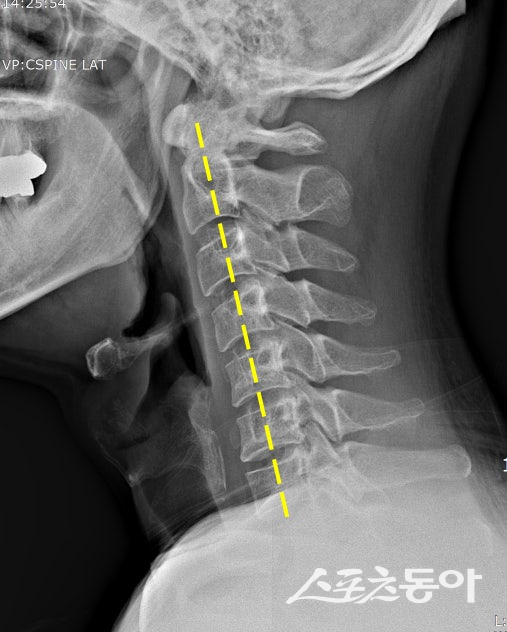

거북목 자세를 보이는 사람의 경추 X-레이. 스포츠동아DB

가장 흔한 거북목은 목을 앞으로 내밀고 고개를 숙인 자세가 원인이다. 벽을 등지고 서서 뒤통수, 어깨, 엉덩이를 벽에 붙인 채 턱을 살짝 당기면 목의 정렬을 바로잡는 데 도움이 된다. 고개를 뒤로 젖혔다가 정면으로 되돌리는 동작을 10회 반복하는 것도 효과적이다.